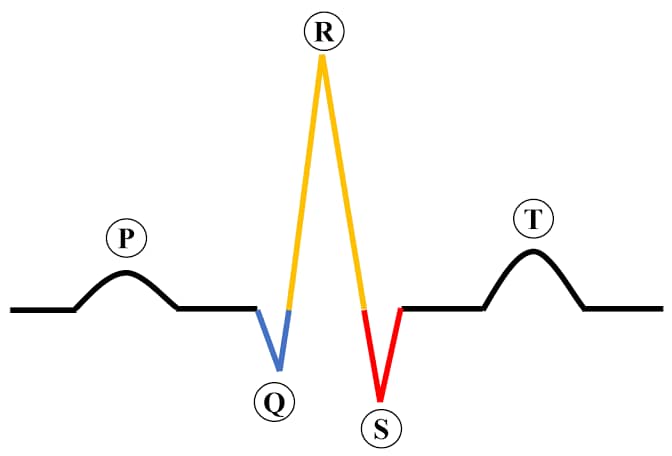

ECG

ECG simply means ElectroCarDiogram. It is described as a medical test records the electrical signals in the heart. That is, as the heart beats, it is ECG that measures the electrical activities which are displayed as a graph or trace. In addition to this, It has so many uses in the medical fields. It helps to diagnose heart attacks, assess the effectiveness of heart medications, also evaluate heart-related problems like fatique, dizziness….and so on.